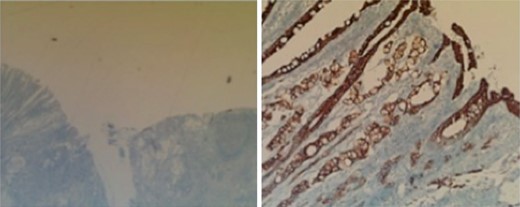

Subsequent surgical pathology results confirmed two separate malignant processes causing the carcinomatosis: Immunohistochemical examination was performed on the surgical specimens. The appendiceal tumor stained negative for CK-7 and positive for CK-20 (Fig. 1), whereas the ovarian sample stained positive for CK-7 and negative for CK-20 (Fig. 2), consistent with malignant processes of independent origins.

Perforated mucinous adenocarcinoma of the appendix arising from villous adenoma, at least 8.5 cm invading into subserosa and into adjacent ileal and cecal serosa with widespread involvement of omentum (carcinomatosis).

Left perforated ovarian mucinous adenocarcinoma with widespread involvement of fallopian tube and subserosa of sigmoid colon (carcinomatosis).